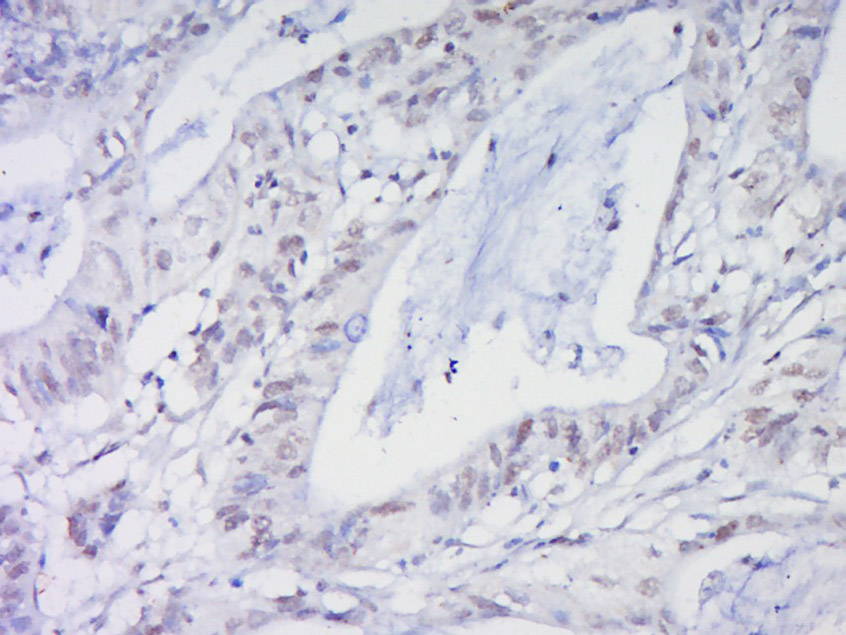

Paraformaldehyde-fixed, paraffin embedded (Human cervical cancer); Antigen retrieval by boiling in sodium citrate buffer (pH6.0) for 15min; Block endogenous peroxidase by 3% hydrogen peroxide for 20 minutes; Blocking buffer (normal goat serum) at 37°C for 30min; Antibody incubation with (Hox-3.1) Polyclonal Antibody, Unconjugated (bs-0394R) at 1:500 overnight at 4°C, followed by a conjugated secondary (sp-0023) for 20 minutes and DAB staining.